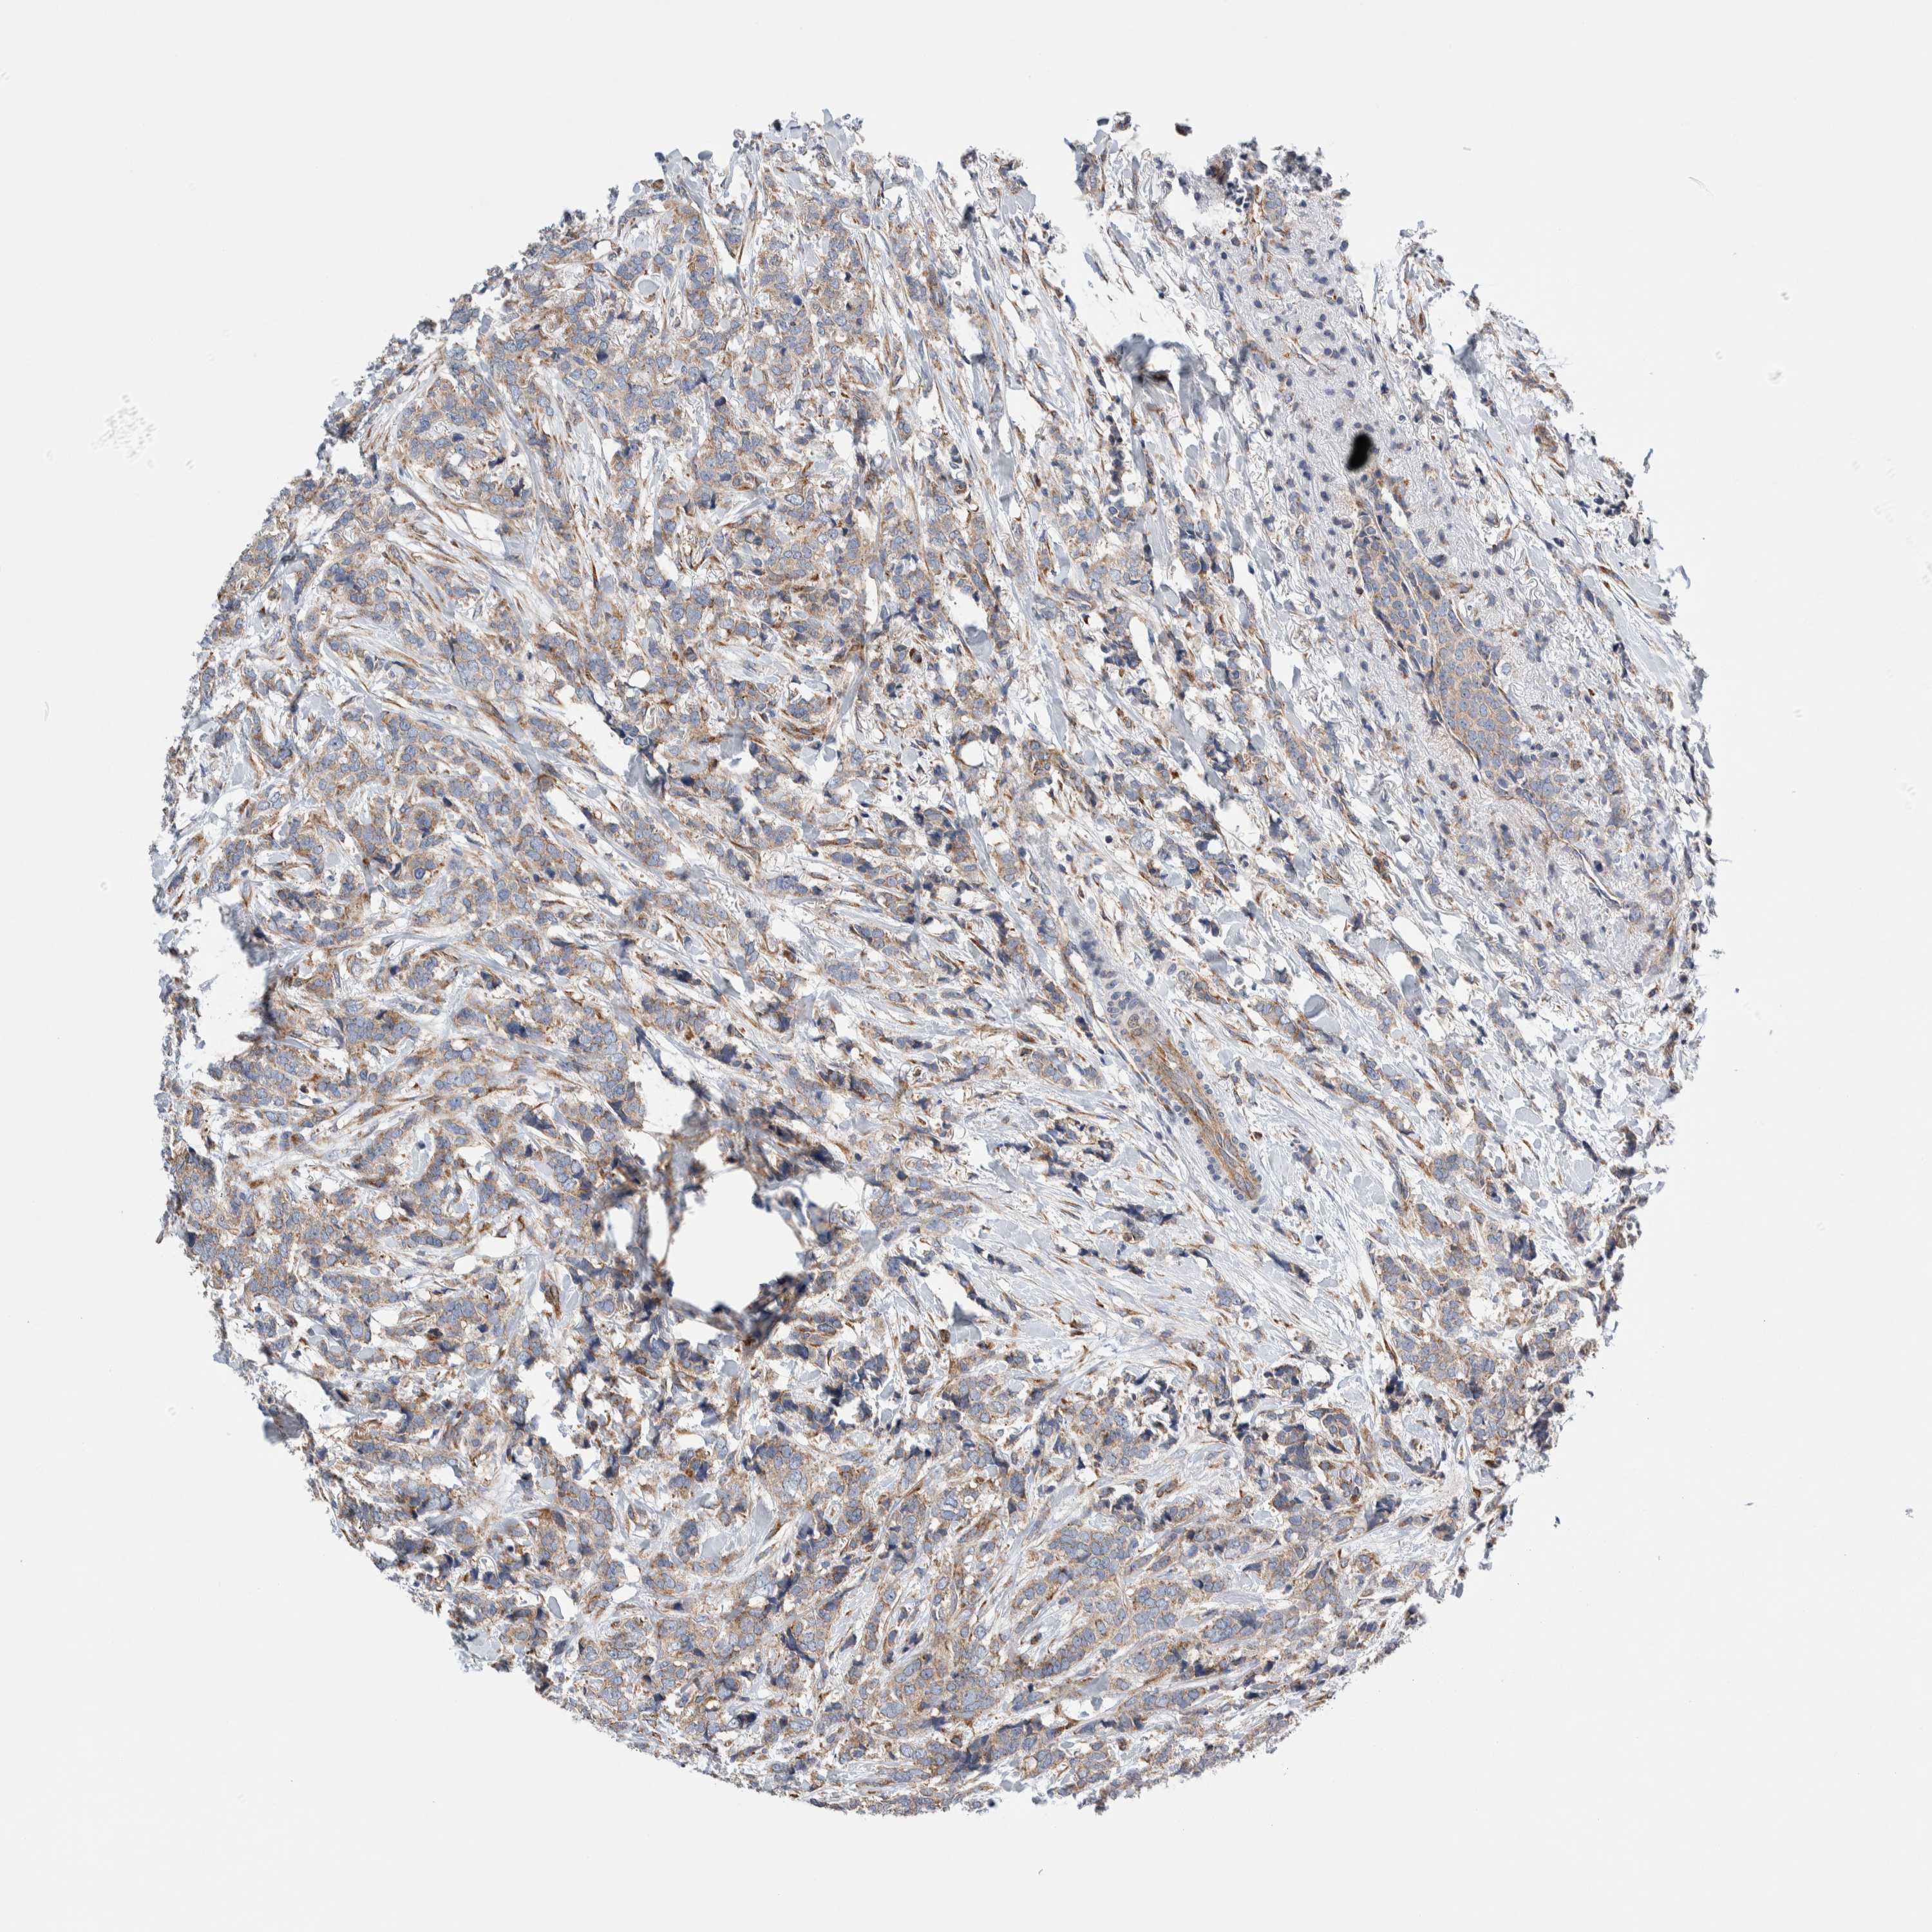

Breast cancer

Human cancer